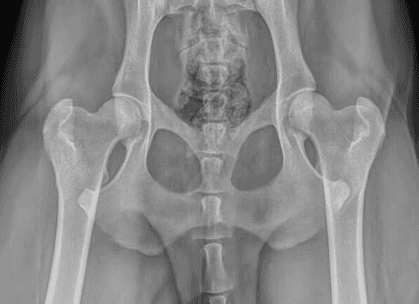

Canine Hip Dysplasia (CHD) is one of the most common causes of hindlimb lameness in dogs,

with genetics playing a major role in its development. The condition begins during early growth when there is laxity (looseness) in the hip joint.

Normally, the femoral head (ball) fits snugly within the acetabulum (socket), allowing smooth motion and even joint development. When the joint is too loose, abnormal forces lead to uneven growth of the bones, stretching of the joint capsule, asymmetric cartilage wear, and bone remodeling. Over time, these changes result in cartilage loss, scar tissue formation, and the development of bone spurs (osteophytes).